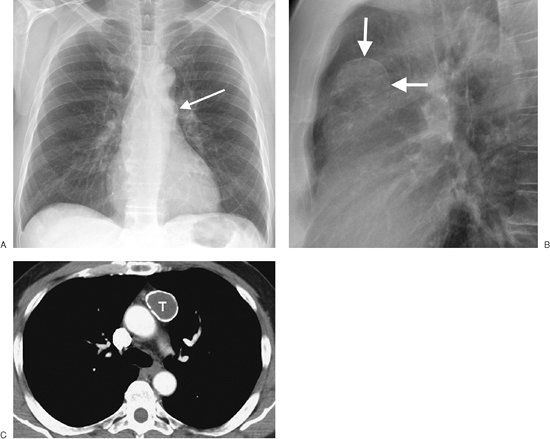

FIGURE 6-30. Bronchogenic cyst. PA (A) and lateral (B) chest radiographs of a 23-year-old man show a round mass in the left medial hemithorax (arrows). C: CT scan shows that the nonenhancing left hilar mass is of homogeneous fluid attenuation, consistent with a cyst (C).

Bronchogenic cysts have a fibrous capsule, often contain cartilage, are lined with respiratory epithelium, and contain mucoid material. Most arise in the mediastinum or hilar areas, but they can also arise within the lung parenchyma. These cysts can rapidly increase in size as a result of hemorrhage, infection, or distension with air, indicating communication with the airways. They are seen on chest radiographs as well-defined

P.93

solitary masses in the mediastinum or hilum (Figs. 6-29 and 6-30) and are usually found in close proximity to the major airways. The single most frequent site is between the carina and the esophagus. Calcification, either rim calcification or milk of calcium within the cyst, has been described (18). CT scans usually show a simple cystic mass with an imperceptible or thin smooth wall. The CT attenuation is generally that of water (-10 to +10 Hounsfield units) but can be higher (as high as 120 Hounsfield units) when filled with milk of calcium or proteinaceous material that accumulates after infection or hemorrhage (Fig. 6-31). The cysts can be unilocular or multilocular. Curvilinear calcification of the wall can be seen.